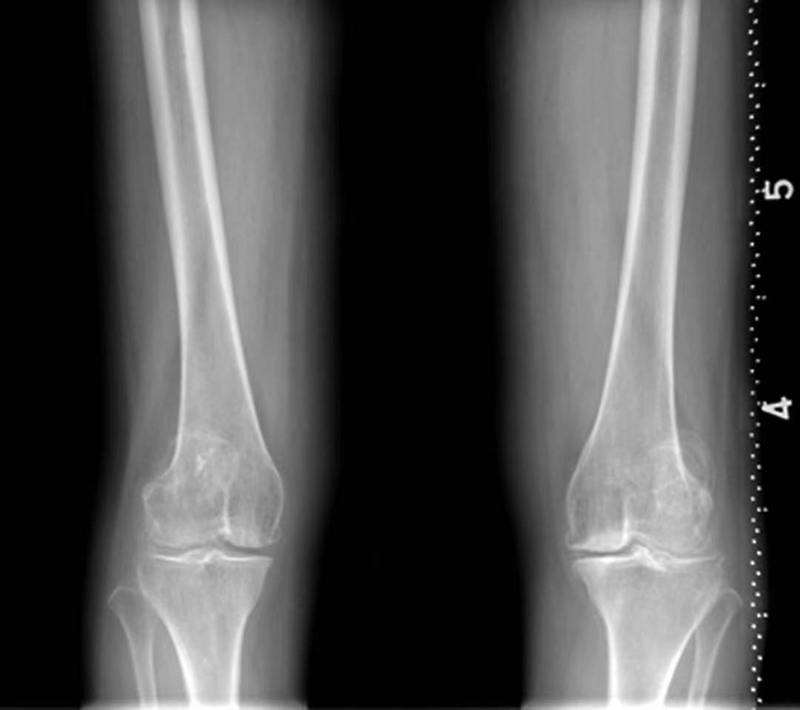

可以发现髌骨(图7~图9)和股骨-胫骨髁(图10)的发育不良、畸形及股-胫间隙变窄等异常(图11、图12)。

图11 双侧膝关节内翻,诸组成骨边缘可见骨赘形成。关节间隙不等宽,内侧较外侧窄。关节面可见骨质硬化及小囊变,关节囊肿胀

图12 双膝外翻,关节间隙不等宽,外侧较内侧窄。关节面可见骨质硬化